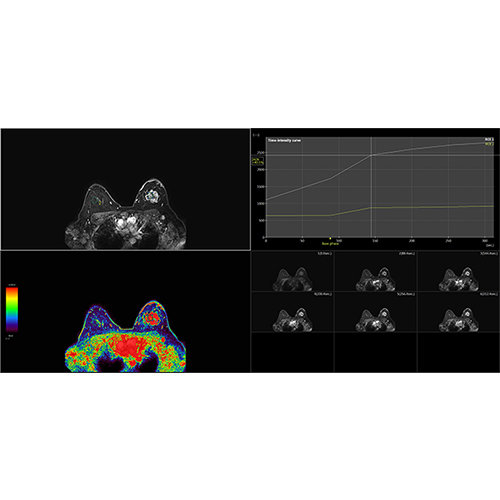

ANYTHINK 经导管主动脉瓣膜置换术分析系统